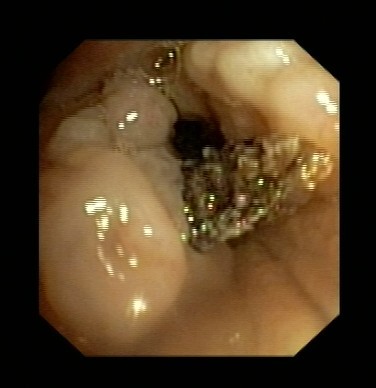

近日,吕先生有门诊收入我呼吸科住院治疗,全体医护人员高度重视,认真讨论病情。我科吴主任仔细看过吕先生的CT片后,观察到右下肺气管内异物,于是决定行支气管镜检查。在气管镜室,吴主任给他做了支气管镜检查,发现吕先生右下肺支气管内卡着一个黑黑的异物,由于时间太久,异物周围已充血水肿,表面有脓苔及坏死物覆盖,清除脓苔及坏死物后,可见异物被肉芽组织紧紧包埋。吴主任成功取出了吕先生气管内异物,并吸出了气管内脓性分泌物。吕先生咳嗽症状立刻改善,行气管镜检查后第二天患者无咳嗽症状,顺利出院。

图表1气管内异物被坏死物包裹